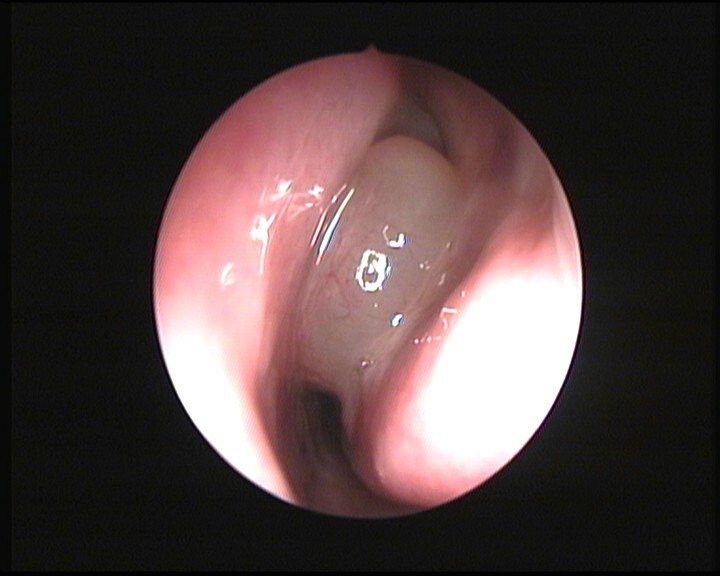

La prima manifestazione dei polipi è un ispessimento diffuso o circoscritto associato ad un rigonfiamento della mucosa. Se i fattori eziologici continuano ad agire, il passaggio successivo è la formazione di un’area mucosa alterata, a base ampia, più o meno definita, dalla quale si sviluppano i polipi. L’aspetto di queste neoformazioni è di solito traslucido, di consistenza molle e colore giallastro, anche se non mancano variazioni in relazione al tipo di paziente ed all’estensione della patologia. La diagnosi viene effettuata dallo specialista otorinolaringoiatra durante la visita ambulatoriale che deve essere effettuata con l’endoscopia nasale. Questa metodica strumentale è necessaria per una corretta valutazione della patologia ed inoltre, se l’endoscopio viene collegato ad una telecamera ed a un monitor, consente al medico di illustrare con chiarezza il quadro clinico al paziente. Per valutare l’estensione e la gravità della poliposi nasale è necessaria la Tomografia Computerizzata (TC) che consente di analizzare in dettaglio le strutture anatomiche coinvolte dalla patologia. (Fig. 2)